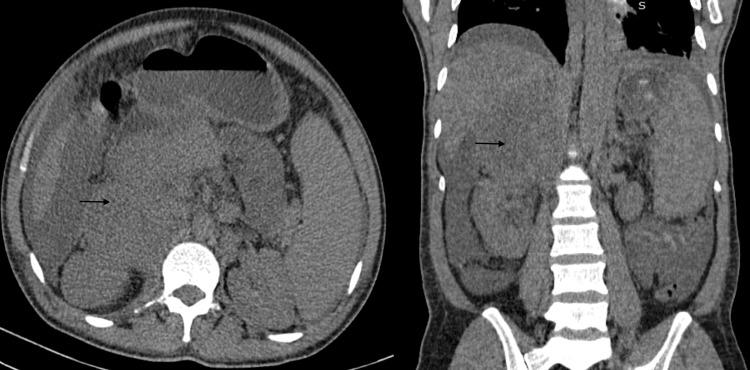

Adrenocortical carcinomas are rare but aggressive tumors that are frequently discovered as incidentalomas. Secretory tumors often lead to endocrine abnormalities, namely cushingoid features, virilization, or feminization. Non-functioning tumors, on the other hand, can be completely dormant with an insidious course or cause malaise, weight loss, abdominal pain, etc. Biochemical testing must be pursued in all patients with incidentalomas to detect pheochromocytoma, excess cortisol, or aldosterone secretion. In this report, we describe the case of a 37-year-old man who was lost to follow-up for two years following diagnosis with adrenal incidentaloma. This led to delayed diagnosis of adrenal carcinoma and eventual mortality. Periodic surveillance of adrenal incidentalomas is therefore imperative for timely interception of malignant lesions.

肾上腺皮质癌罕见但具有侵袭性,常作为意外瘤被发现。分泌性肿瘤常导致内分泌异常,即库欣样特征、男性化或女性化。另一方面,无功能肿瘤可能完全潜伏,病程隐匿,或引起不适、体重减轻、腹痛等。对于所有意外瘤患者都必须进行生化检测,以检测嗜铬细胞瘤、皮质醇过量或醛固酮分泌情况。在本报告中,我们描述了一名37岁男性的病例,他在被诊断为肾上腺意外瘤后失访两年。这导致肾上腺癌的诊断延迟并最终死亡。因此,对肾上腺意外瘤进行定期监测对于及时发现恶性病变至关重要。